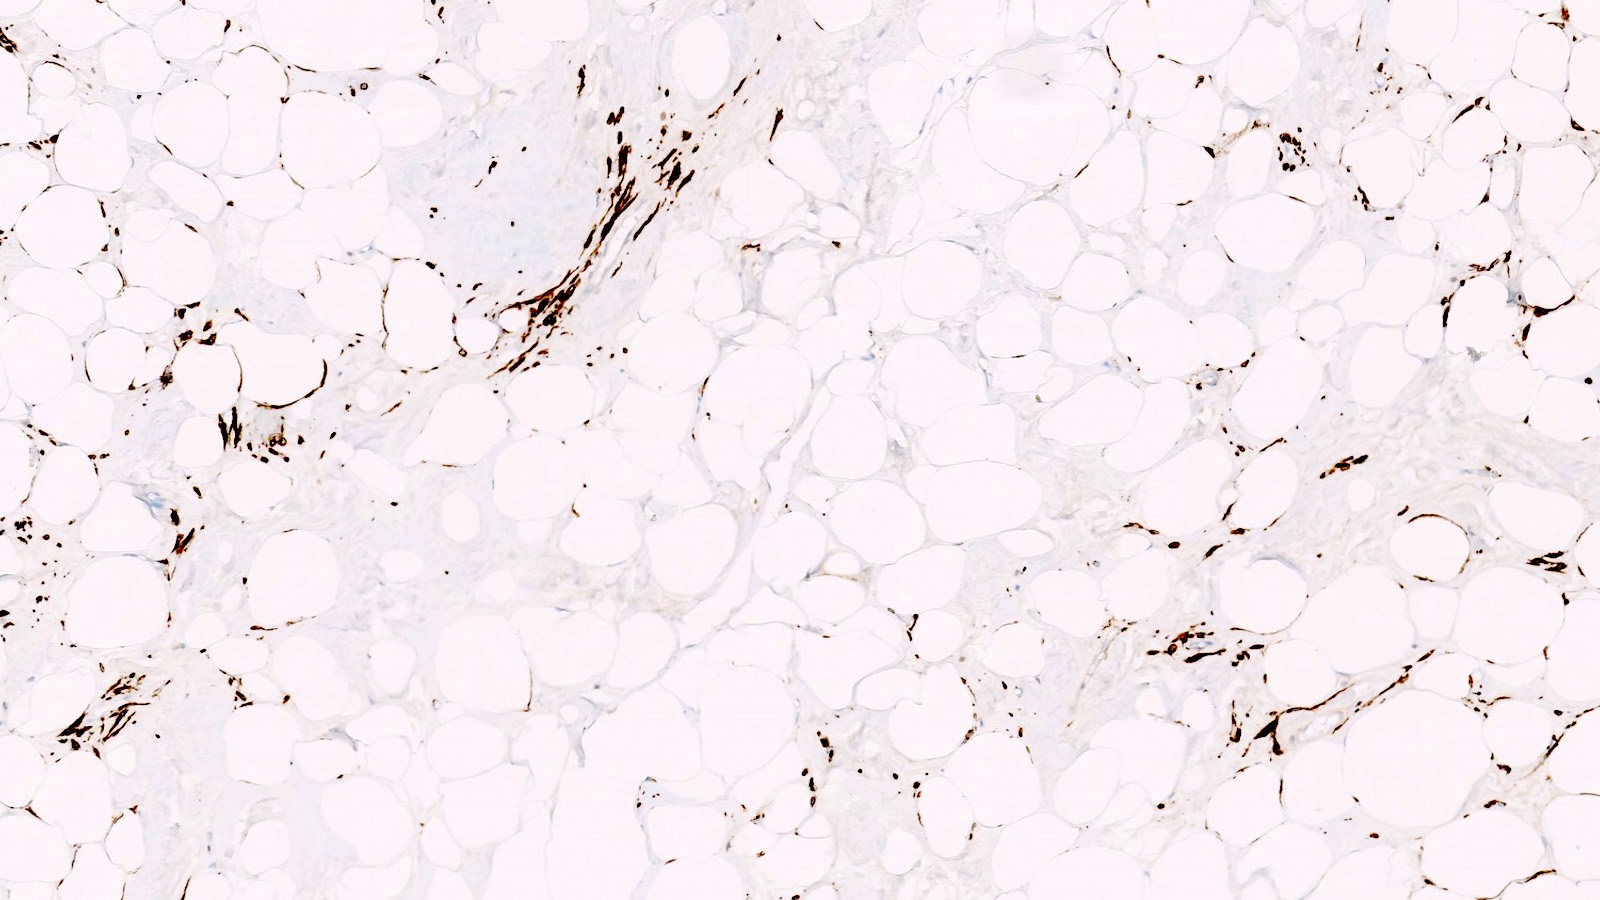

- Lipoleiomyoma:

- Tumor composed of smooth muscle cells mixed with mature adipocytes (variable quantity)

Positive stains

- Desmin

- h-caldesmon

- Smooth muscle actin

- Transgelin